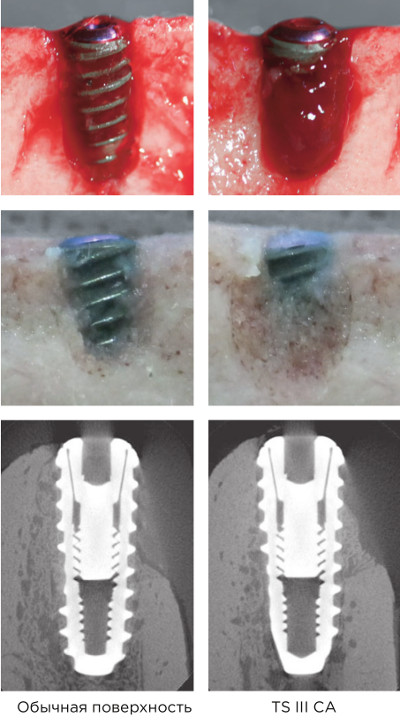

Формирование кровяного сгустка

На фото: сравнение качества кровяного сгустка (после погружения в кровь на 20 мин.).

Усиление адсорбции протеинов в 2,5 раза по сравнению с другими имплантатами.

На фото: сравнение площади адсорбции (поверхность обработана фосфором).

Усиление адгезии тромбоцитов на 38% по сравнению с другими имплантатами.

На фото: сравнение активности (после адгезии клеток), красным - эритроциты, жёлтым - нити фибрина.